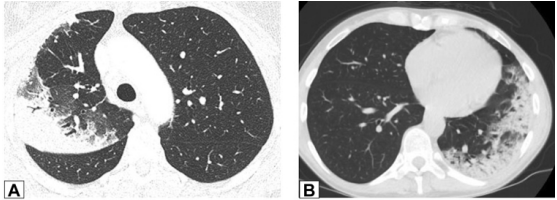

实变是OP病例中最常见的发现,发生于近75%的病例中,病变通常在双基底、支气管血管周围和/或外周。图1A为一名女性患者,右肺上叶周围实变,其曾因乳腺癌接受过放射治疗,并经活检证实为OP。图1B患者左肺下叶和舌叶周围实变,活检证实为继发于淋巴瘤化疗的OP。

图源:Chest, 2022, 162(1):156-178.